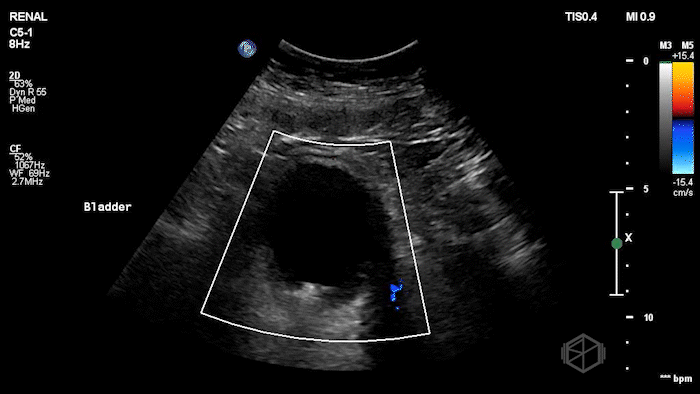

A 70's male with a history of nephrolithiasis presented to the ED with right flank pain worse over the last 4 days. Dr. Mendelow performed a POCUS immediately that showed:

Subsequent CT scanning later showed a 10 x 7 x 7mm right ureterovesical junction calculus within the urinary bladder causing moderate right hydroureteronephrosis, delayed nephrogram and mild perinephric fat stranding. The patient was taken to the OR for scope of bladder and right ureter; laser lithotripsy and removal of right ureteral stone and placement of right ureteral stent.

Diagnosis: 10mm UVJ stone with moderate hydronephrosis

• Not all stones twinkle — Twinkle artifact has limitations. Doppler twinkling artifact has low sensitivity (~54%) but high specificity (~95%) for detecting urinary stones, meaning a missing twinkle does not rule a stone out

(📚 PMID: 31700749).

• Color Doppler absence of ureteral jets may suggest obstruction. Most healthy people have a ureteric jet frequency of 2 or more per minute on either side. One study reports sensitivity ~87%, specificity ~96% for detecting ureteral obstruction when less than 25% ejections are seen over five minutes, another found sensitivity to be 94.8% but specificity to be 55.5% (📚 PMID: 37465268).

• The practical utility is debated—bilateral strong jets are reassuring, but absence is only meaningful when there’s a high suspicion for unilateral obstruction and no jet is seen after adequate observation. There is no need to wait any longer than 2 minutes at the most (📚 PMID: 16509793).